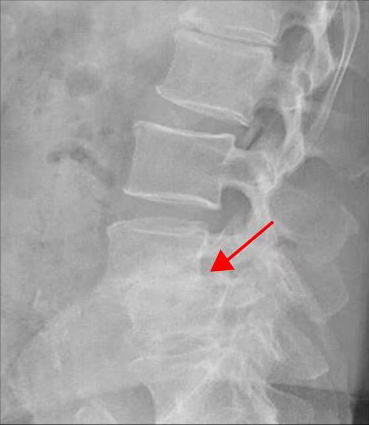

<4-5번 척추전방전위증>

이 환자분의 허리 MRI를 보면 4번, 5번 오른쪽에 심한 추간공협착증과 2단계의 척추전방전위증이 있는데, 특히 척추전방전위증 때문에 추간공이 많이 좁아져 있는 상태입니다. 또 왼쪽의 다른 마디에 디스크 파열이 있으나 환자분이 왼쪽으로는 증상이 전혀 없는 것으로 보아 이 디스크 파열은 통증을 일으키지 않는 무증상의 디스크 파열입니다.

이렇듯 4번, 5번 마디의 심한 추간공협착증과 척추전방전위증으로 인해 이 환자분은 다리에 마비가 왔고, 발목에 힘이 빠져 거의 걷지 못하는 상태였습니다. 새벽에 잠에서 깨 화장실을 갈 때는 네 발로 기어갈 정도로 증상이 심했습니다. 신경주사도 많이 맞아봤지만 통증이 전혀 줄지 않아서 결국 수술을 결심하셨는데요. 대학병원을 비롯해 정형외과 및 신경외과 등 아홉 군데 병원에서 진료를 받았지만, 어려운 수술이라고 말하면서 척추유합술, 감압술 등 병원마다 제시하는 수술방법이 다 달라 큰 혼란을 겪으셨습니다. 게다가 수술 후 후유증이나 잔존 증상에 대한 물음에 ‘있을 수도 있고 없을 수도 있다’라는 의사의 말에 수술을 고민하던 중 마지막이라는 생각으로 저희 모커리에 내원하셨습니다.